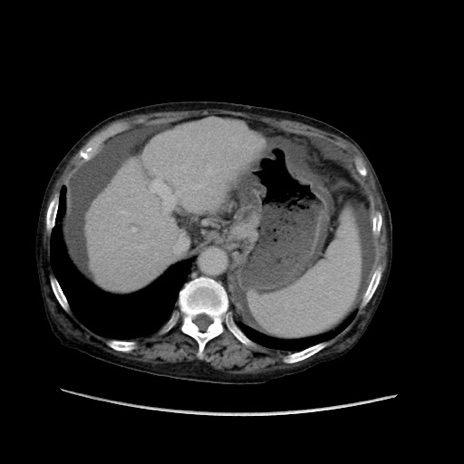

症例31(横断像)

【症例】80歳代 女性

【主訴】腹部膨満感

【現病歴】他院にて肝硬変にてフォロー中。1週間前から便秘、腹部膨満感、臍部腫瘤あり受診となる。

【既往歴】肝硬変

【身体所見】腹部膨隆あり、皮膚変化なし、疼痛なし。

【データ】WBC 4600、CRP 0.25